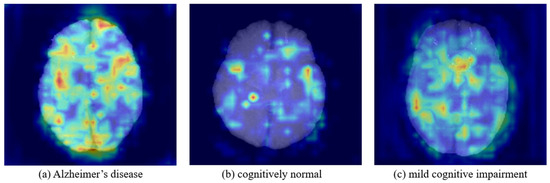

Deep learning-based analysis of brain magnetic resonance imaging (MRI) plays a crucial role in the early diagnosis of Alzheimer’s disease (AD). However, data scarcity and racial bias present significant challenges to the generalization of diagnostic models. Large-scale public datasets, which are predominantly composed of Caucasian individuals, often lead to performance degradation when applied to other ethnic groups owing to domain shifts. To address these issues, this study proposes a two-stage transfer learning framework. Initially, a 3D ResNet model was pretrained on a large-scale Alzheimer’s disease neuroimaging initiative (ADNI) dataset to learn structural brain features. Subsequently, the pretrained weights were transferred and fine-tuned on a small-scale Korean dataset utilizing only 30% of the data for training. The proposed model achieved superior performance in classifying mild cognitive impairment (MCI), which is crucial for early diagnosis, compared with a model trained from scratch using 70% of the Korean data. Furthermore, it effectively mitigated the significant performance degradation observed when directly applying the pretrained model, demonstrating its ability to resolve the domain-shift issue. This study explored the feasibility of transfer learning to address data scarcity and domain shift issues in AD classification, underscoring its potential for developing AI-based diagnostic systems tailored to specific ethnic populations. Full article